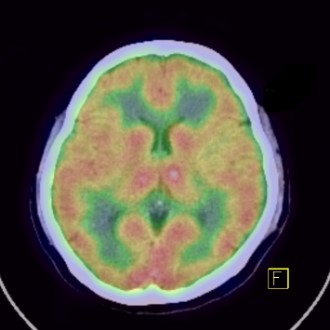

脳血流シンチ

この検査は、脳血管障害や認知症の診断、またてんかんの焦点診断などで用いられます。当院で使用する放射性医薬品は99mTc-ECDというもので、薬品投与直後から30分程度で終了します。この検査で得られた画像から脳内の血流の分布状態を確認し、血流量を算出することができます。また画像統計解析ソフトを使用することで年代別で正常な方々との比較を行うことができます。

定性画像(分布状態) CTとのFusion画像